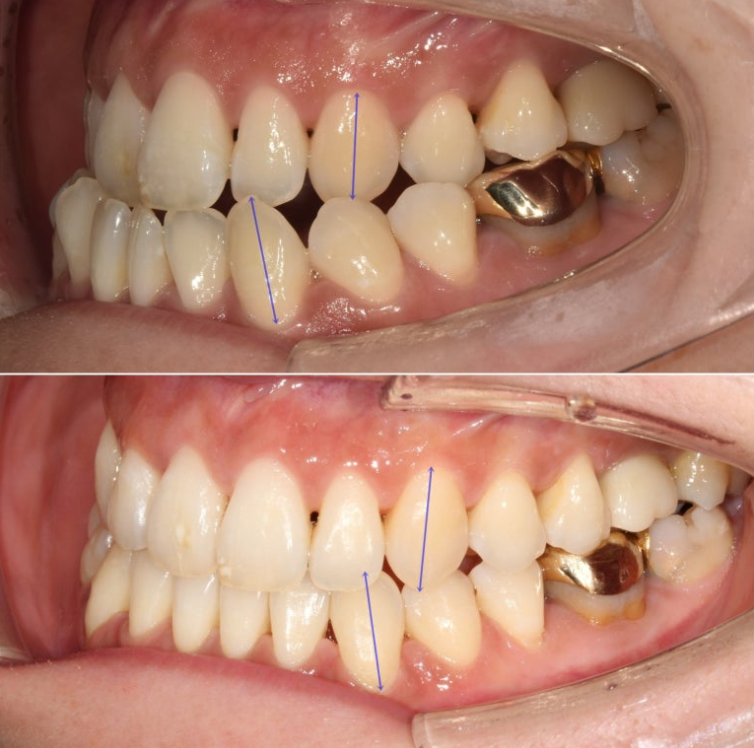

아래 전체치열을 사랑니 공간을 이용하여 뒤로 밀어내어 최종적으로 아래 앞니가 뒤로 움직이고 앞니 교합을 정상화 시키기로 합니다.

앞니 반대교합은 해소가 되었고 아래 앞니 배열이 개선되면서 생긴 블랙트라이앵글이 보입니다.

아직은 어금니가 뜨고 교합이 잘 안되는 상태입니다.

블랙트라이앵글은 아쉽지만 중심선은 거의 맞고 교합이 깔끔해졌습니다.

앞니 뿐만 아니라 어금니 반대교합도 함께 개선되었습니다.

중심선은 개선되었습니다.